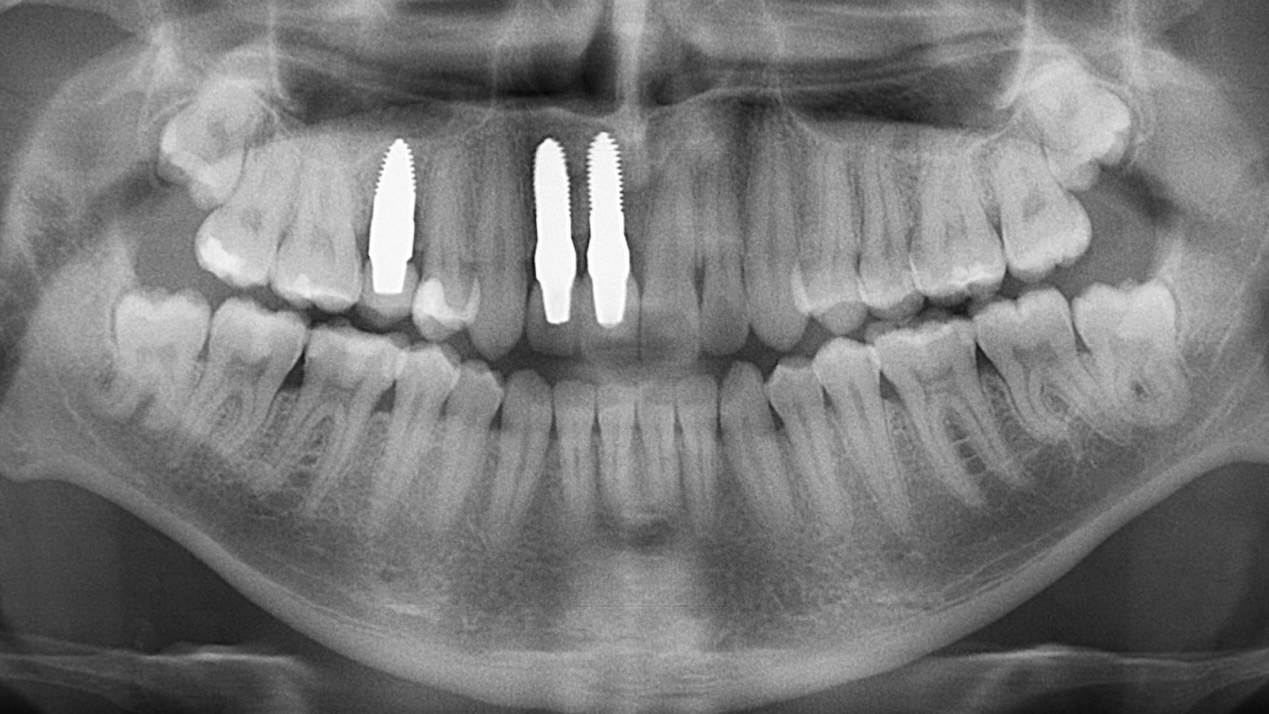

The poster provided a clear and structured overview of the pre-, intra-, and postoperative stages of ceramic implant placement, illustrating:

the biological reasoning behind treatment decisions,

the dynamics of soft- and hard-tissue healing,

and the long-term functional and aesthetic outcomes achievable with ceramic implants.